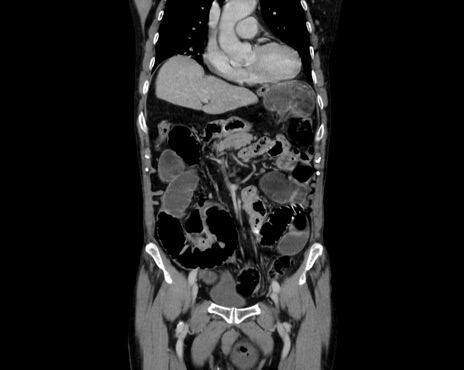

症例26(冠状断像)

【症例】80歳代男性

【主訴】嘔吐

【現病歴】昨晩2回嘔吐あり、今朝になっても嘔吐あり。来院。

【既往歴】胃潰瘍

【身体所見】意識清明、BT 37.6℃、BP 166/95mmHg、HR 100bpm、SpO2 97%、腹部:平坦・軟、腸蠕動音聴取良好、圧痛なし。

【データ】WBC 21900、CRP 1.4